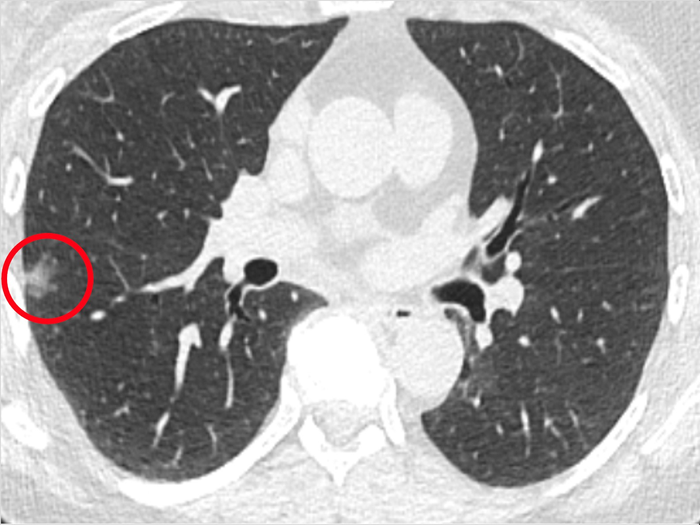

PHILADELPHIA — Researchers at the Abramson Cancer Center at the University of Pennsylvania have found a way to identify lung cancer at the cellular level in real time during a biopsy, offering promise in the ability to detect the disease earlier and with more confidence. The findings, which build on previous Penn research, demonstrate that an imaging agent detected via guided technology during biopsies in real time can effectively light up cancer cells that may have been too small to detect using existing technology. Based on the more easily identifiable presence of fluorescent cancer cells generated by the new imaging approach, five non-expert raters diagnosed the malignant or non-malignant tissue biopsies with 96 percent accuracy and made no false negatives on the 20 human biopsy specimens they reviewed. The research is published this week in Nature Communications .

The Penn team examined human cancer cells from patients who had a history of smoking. Researchers took the cancer cells and grew them with the normal cells in the laboratory to see how small a quantity of cell could be detected. Then, with an investigational imaging agent, Cytalux™ (pafolacianine) injection, paired with Cellvizio ® , a probe and needle-based imaging platform, they discovered that integrating the technologies allowed researchers to detect cancer at the cellular level in real time during biopsy in various preclinical models, including in culture, small animal models, and human tissue from patients undergoing surgery for lung cancer as part of an ongoing clinical trial. The researchers call the new technology NIR-nCLE, as it combines the cancer-targeted near-infrared (NIR) tracer with a needle-based confocal laser endomicroscopy (nCLE) system, which is modified to detect the NIR signal.

Biopsies of suspicious tissue are not always effective, because many times the concerning nodules may be too small to see and to remove for further testing. Not only does this leave many patients and physicians uncertain about whether cancer is present, it requires the need for additional biopsies and radiological surveillance until the nodule is big enough to see for removal and evaluation via a histopathologic evaluation, which can take several days to complete. Current medical technology does not provide real-time diagnostic information during biopsy.

Methods like NIR-nCLE, which aim to find these microscopic nodules, can offer greater precision in the identification and, later, removal of cancer cells.